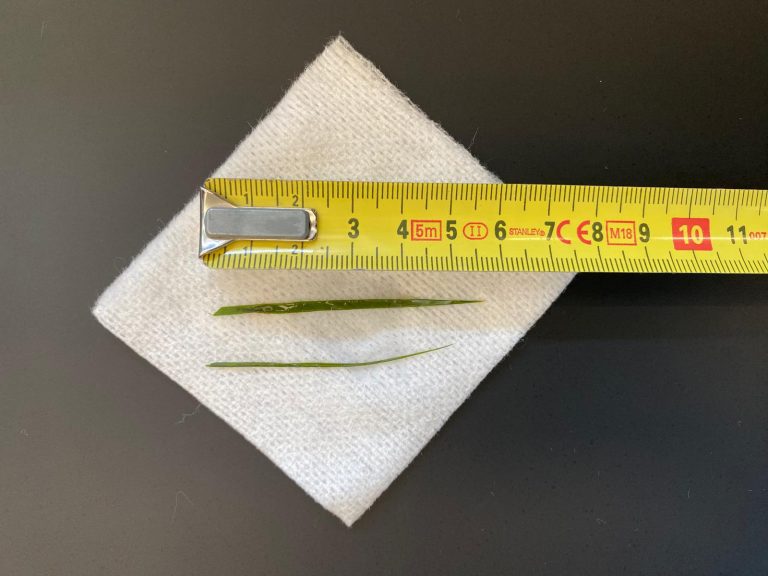

De hoeveelheid lucht had zich zelfs vermeerderd, wat meer in de richting van een verstopping wees, mogelijk door een vreemd voorwerp. De eigenaren vertelden dat er een latex koetje vermist werd. Helaas is latex meestal niet zichtbaar op een röntgenfoto. De enige mogelijkheid om een verstopping te verhelpen die niet reageert op medicatie, is opereren, dus diezelfde middag werd T-Bone voorbereid voor operatie.